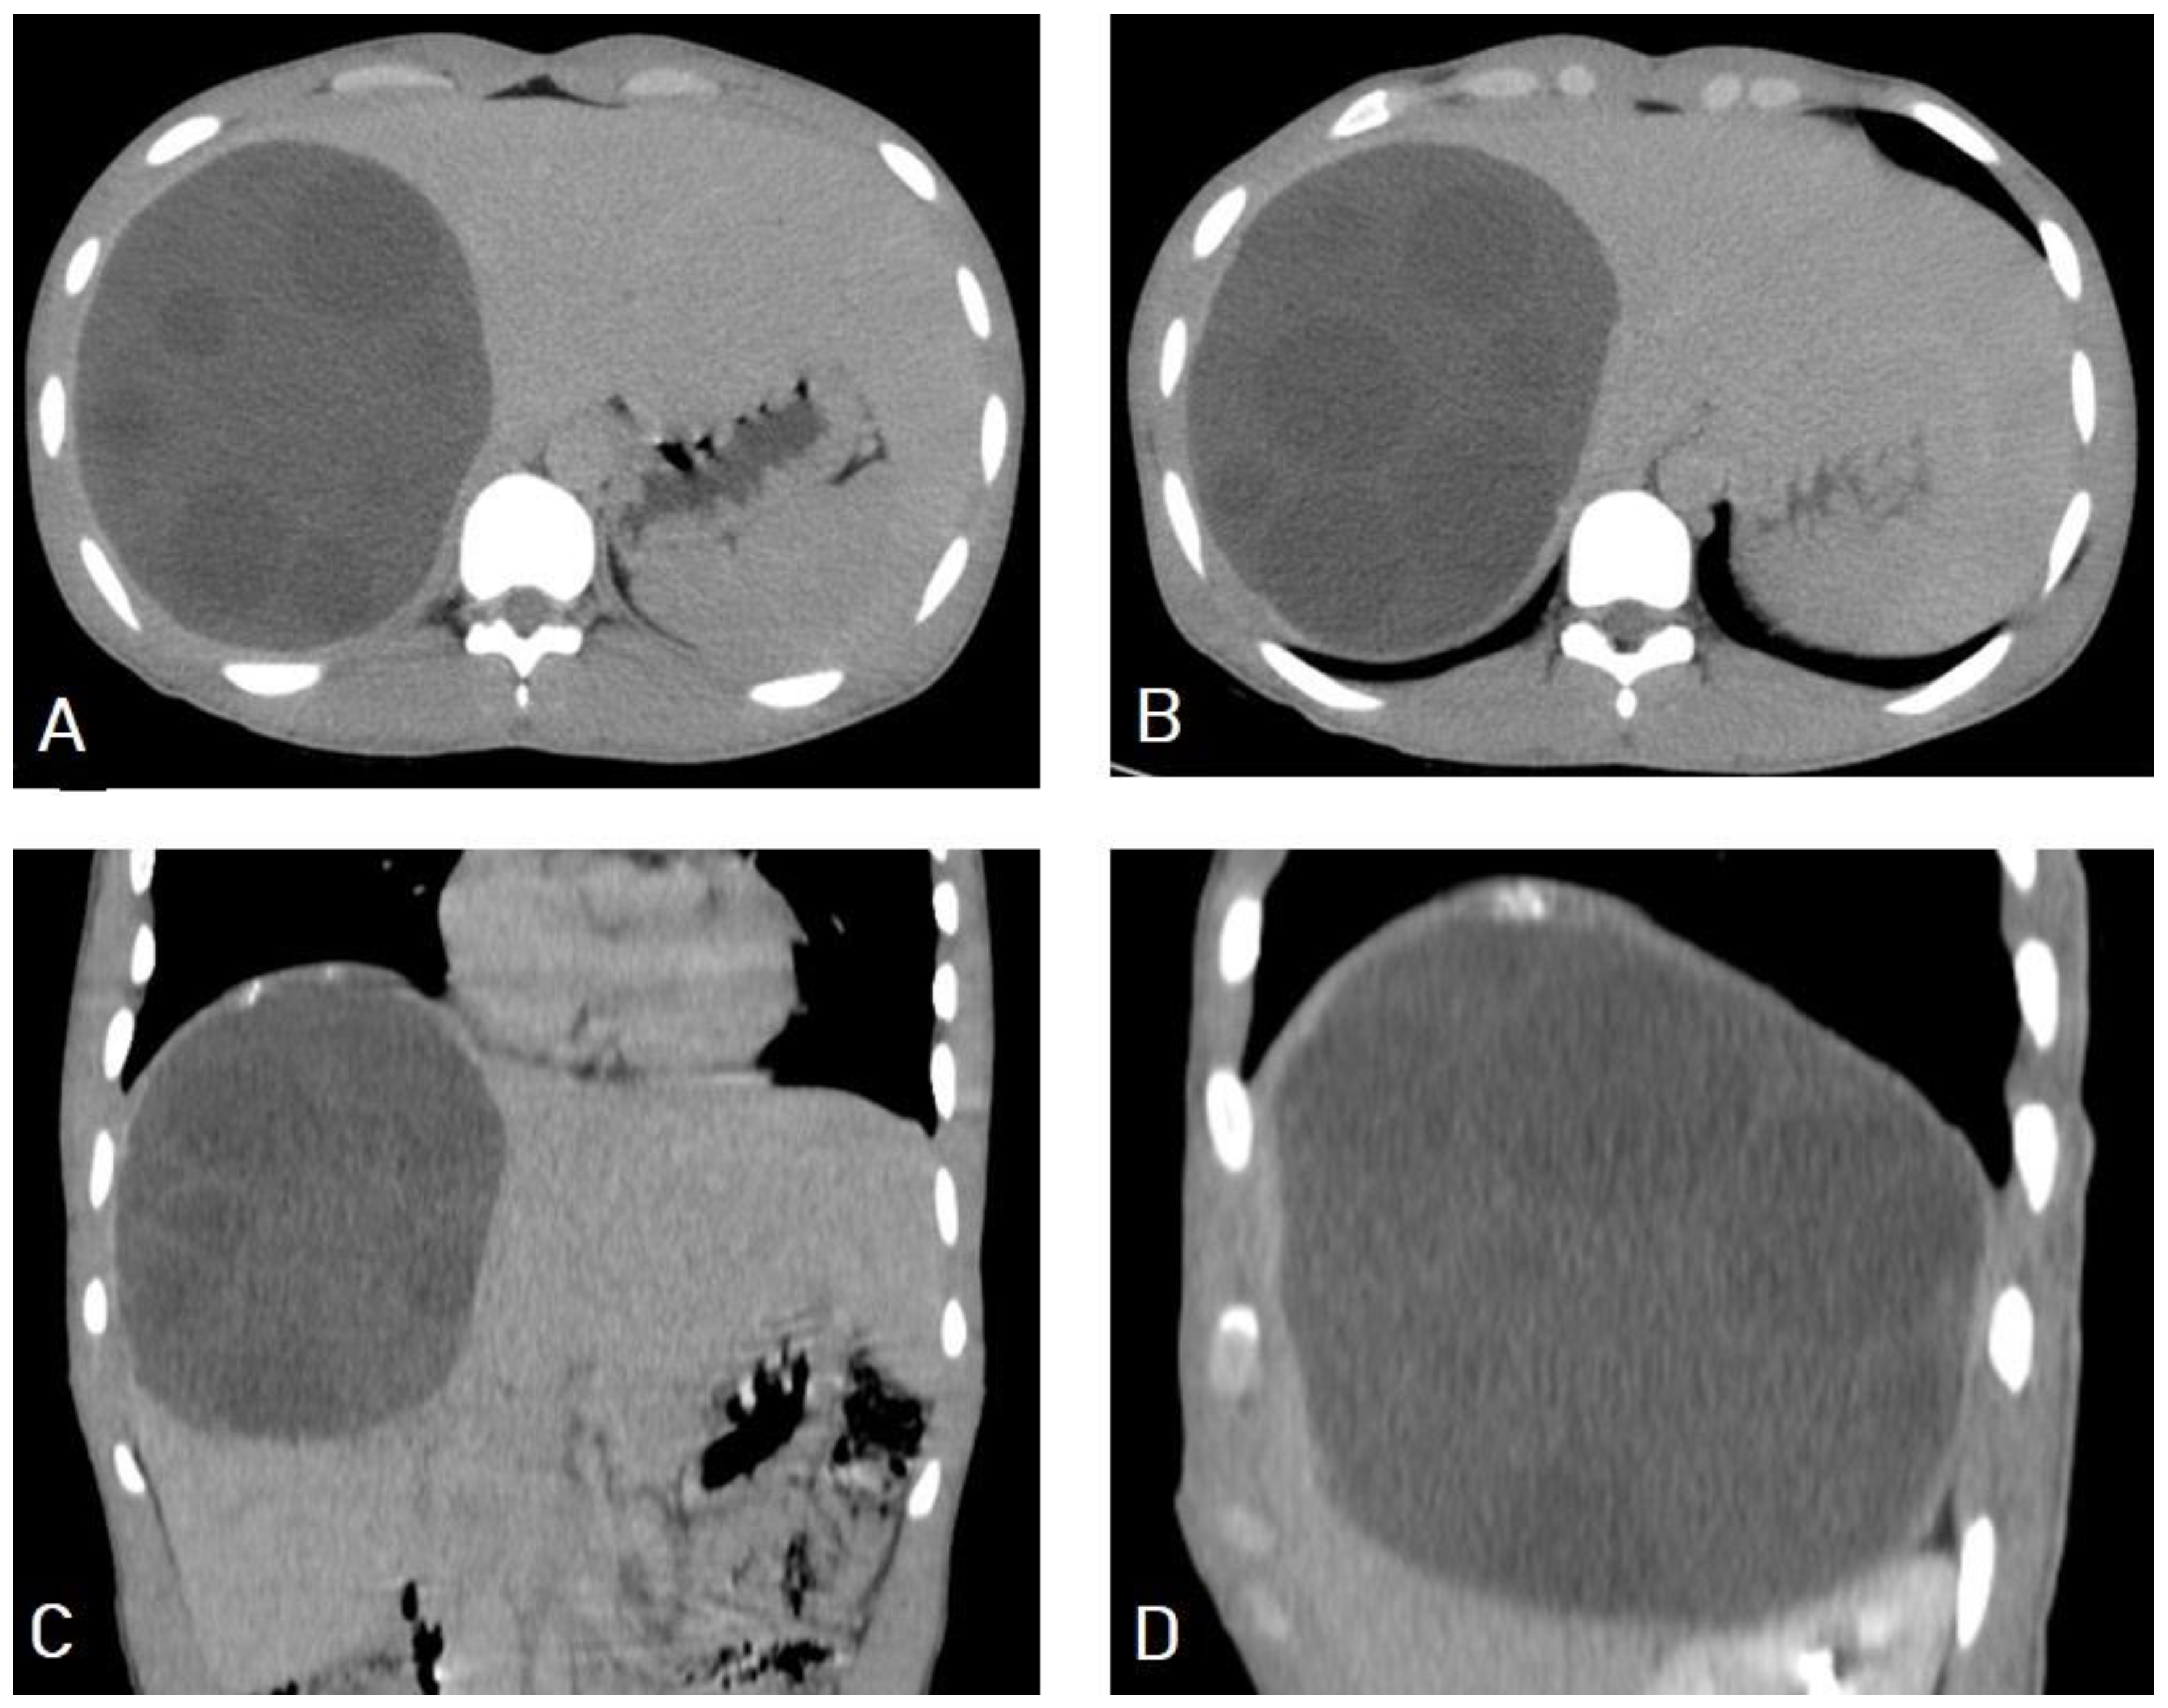

5.1. Hydatid Cysts of the Liver